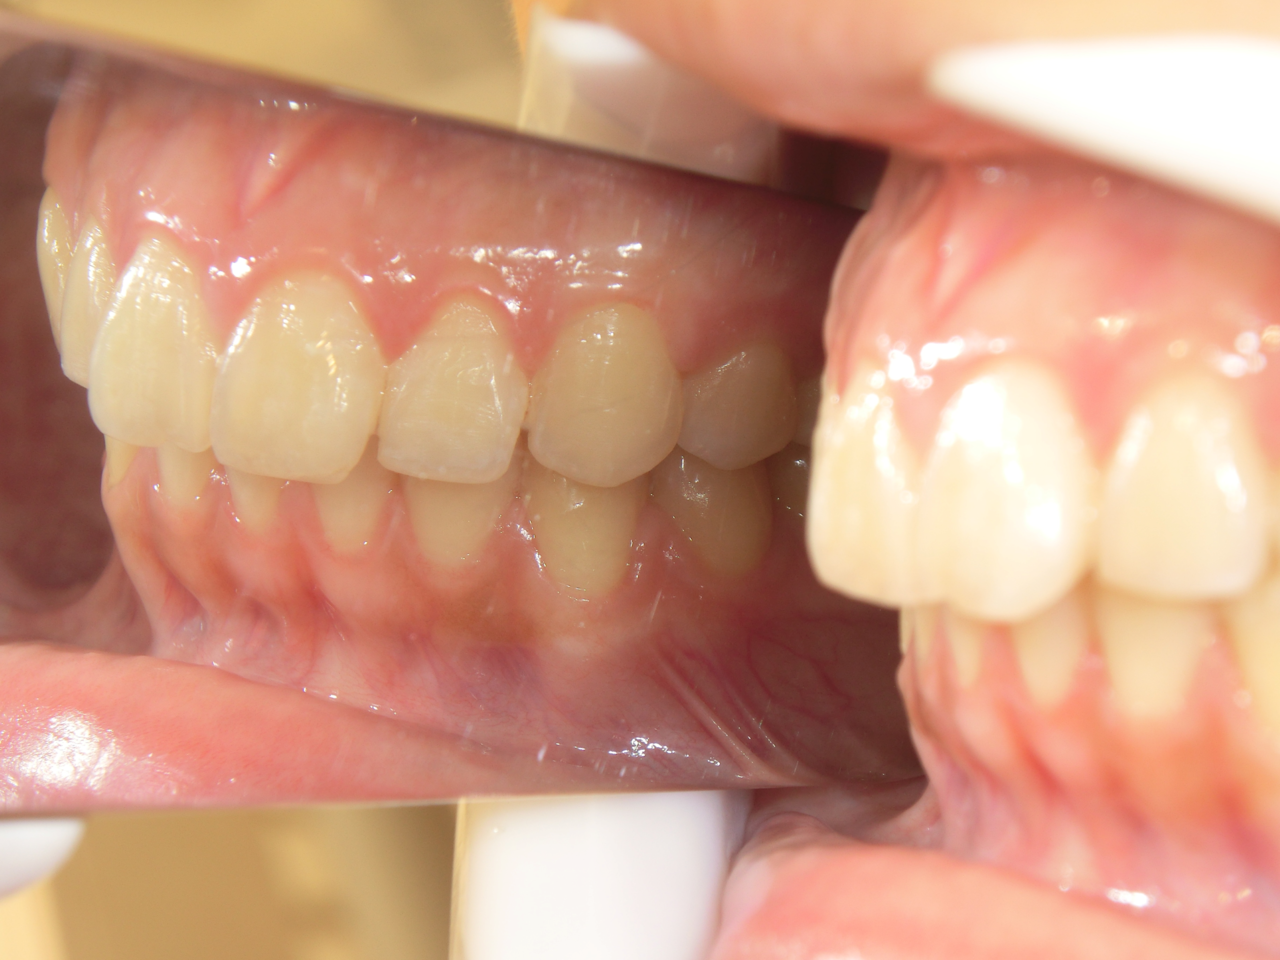

治療前

治療説明 歯科矯正でも目立ちにくい矯正方法であるマウスピース矯正で治療しました

治療期間 2年6か月

治療費用498000 円

治療後

治療の副作用(リスク)歯の動き方には個人差があり、予想された治療期間が延長する可能性があります。。マウスピースの使用状況、矯正歯科治療には患者さんの協力が必要であり、それらが治療結果や治療期間に影響します